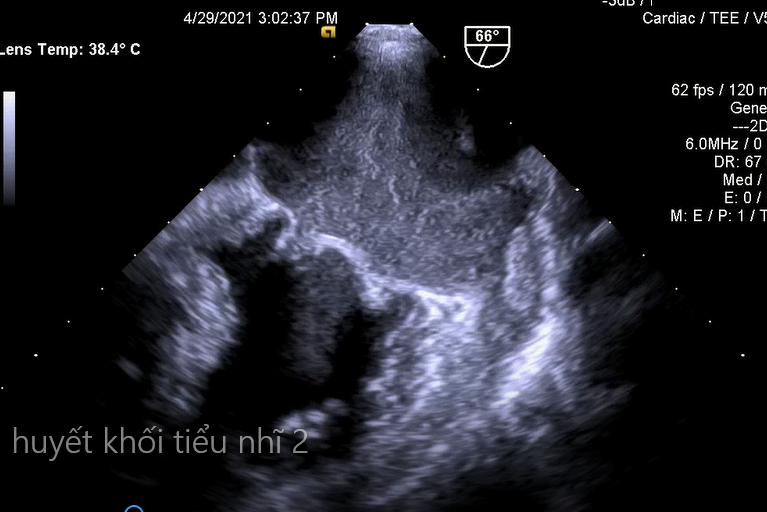

3.Huyết khối tiểu nhĩ trái trên bệnh nhân hẹp van 2 lá (không thấy được trên siêu âm tim qua thành ngực)